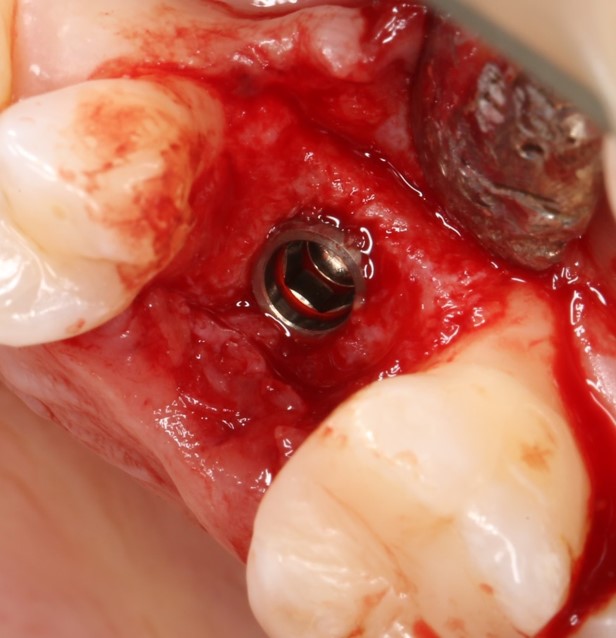

Для решения поставленной клинической задачи мы выбрали имплантационную систему Xive. Из имеющихся у нас трёх имплантационных систем, она лучше всего подходит для немедленной имплантации и немедленной нагрузки, и вот, почему:

В процессе ирригации лунки промываются, что позволило нам еще раз подтвердить ранее сделанные выводы. С помощью аналогов имплантатов, входящих в хирургический набор Xive, мы проверили возможность стабилизации имплантатов в будущих лунках. Исходя из правил подбора и позиционирования имплантатов (я очень рекомендую почитать об этом здесь>>) мы остановились на Xive S диаметром 3,4 мм и длиной 13 мм.

По ряду уже упомянутых выше причин, для решения этой клинической задачи мы выбрали имплантаты Xive. Лунки для них мы уже приготовили. возможную первичную стабильность оценили. Имплантаты мы установили с усилием чуть больше 15-20 Нсм — такого крутящего момента более, чем достаточно, особенно если учесть, что временные коронки будут соединяться между собой.